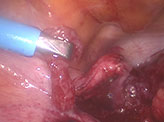

The bowel adhesions near the left adnexa were released by sharp dissection. Bowel adhesiolysis could be only done partially since there was a high risk of bowel injury. At one point, tissue resembling chorionic tissue was seen projecting out from a structure resembling the fallopian tube. Tube could not be identified separately. Chorionic tissue was taken for histopathological examination. Bleeding points were identified from the suspected base of the tube, which was coagulated using microbipolar cautery. Since the vital structures like ureter and iliac vessels were extremely close to the lateral wall, further coagulation of the bleeding points could not be done. Drain was inserted and patient was followed up with serial βhcg. 4 days after the surgery, decreased to 3110 mIU/ml. The following week the value was 526 mIU/ml. She was followed up with expectant management with serial weekly monitoring of βhcg. The value reached negligible limits 5 weeks after surgery.